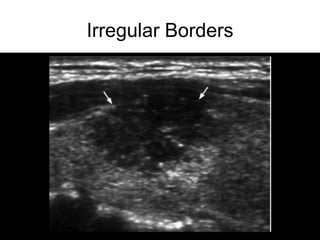

• Irregular borders

Irregular Borders

Ultrasound • Hypoechoic • Increasedcentral vascularity • Incomplete halo • Microcalcifications • Irregular borders • Taller than wide (transverse view) • Suspicious lymph nodes • Hyperechoic • Peripheral vascularity • Complete Halo • Comet-tail • Large, coarse calcifications High Risk Features Low Risk Features